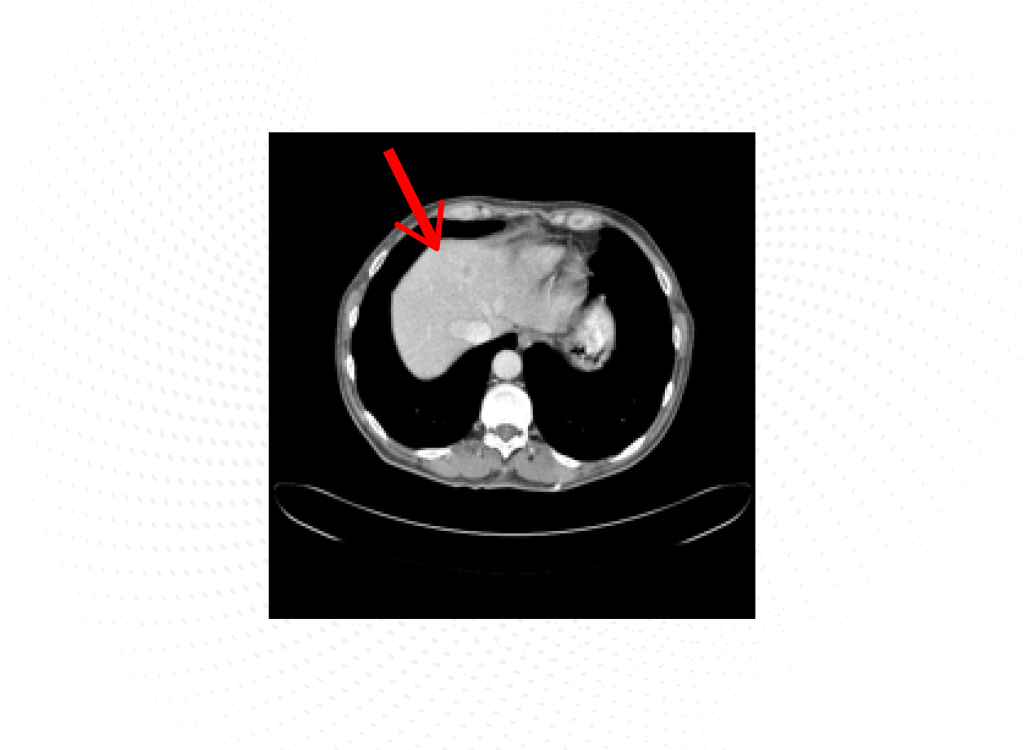

Se procede a su ingreso para completar el estudio y realizar drenaje de la vía biliar. Se propone profilaxis con heparina de bajo peso molecular (HBPM) a dosis profilácticas. Se realiza ecoendoscopia que confirma el diagnóstico de neoplasia de la cabeza del páncreas con adenopatías locorregionales patológicas y se realiza biopsia de la lesión pancreática. Se implanta una prótesis metálica mediante colangiopancreatografía retrógrada endoscópica (CPRE) sin incidencias, con evolución favorable de las cifras de bilirrubina. En el estudio con tomografía axial computarizada (TAC) se confirma el diagnóstico de masa en la cabeza del páncreas, hipodensa, sospechosa de carcinoma de páncreas con atrapamiento de la vía biliar y dilatación de la vía biliar intra- y extrahepática con colédoco de 12 mm de diámetro y metástasis hepáticas (Figura 1). La anatomía patológica de la lesión pancreática demuestra un adenocarcinoma ductal infiltrante pobremente diferenciado de origen pancreático.